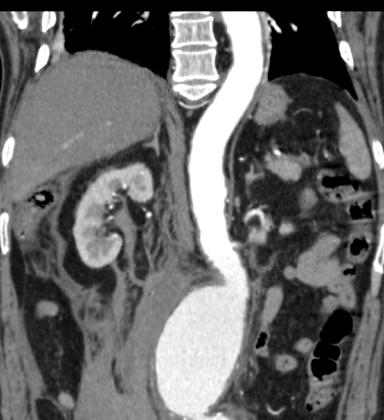

肝脏大小正常、形态规则、包膜完整、各叶比例协调,肝左外叶见以点状密度增高影,肝内胆管和胆总管未见扩张,胆囊形态自然,大小正常,其内未见异常密度影,胰腺形态、大小未见明显异常,脾脏未见增大征象,包膜完整,右肾周及腹主动脉周围,中上腹腔见条带状及片状稍低密度影,形态欠规整。

增强后:腹主动脉下段至左右髂总动脉上端明显扩张,最宽处约6.8cm,上下径约为13cm,成瘤样改变,边界清楚,形态规整。

1.腹主动脉瘤。(腹主动脉下段至左右髂总动脉上端)

3.右肾周及腹主动脉周围,中上腹腔见条带状及片状稍低密度影(多考虑腹腔包裹性积液,请结合临床病史。